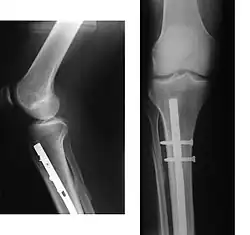

Leczenie złamań może być zarówno zachowawcze (np. opatrunek gipsowy po repozycji, wyciąg bezpośredni), jak i operacyjne.